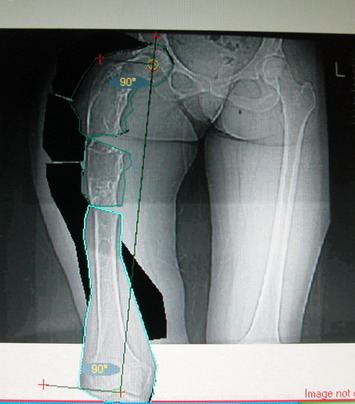

Поскольку в данном случае имеется дело с довольно большой деформацией с укорочением, одномоментная её устранение с внутренней фиксацией, чревато с одной стороны неправильной коррекцией, с другой, нейроваскулярными осложнениями.

Моё мнение, что двойная остеотомия бедра с аппаратом Илизарова + Гексаподный механизм, или Тэйлора, В данной ситуации является методом выбора. Я очень извеняюсь за качество прилагаемых снимков, в которых я постарался отразить разницу междe одной и двумя остеотомиями бедра.